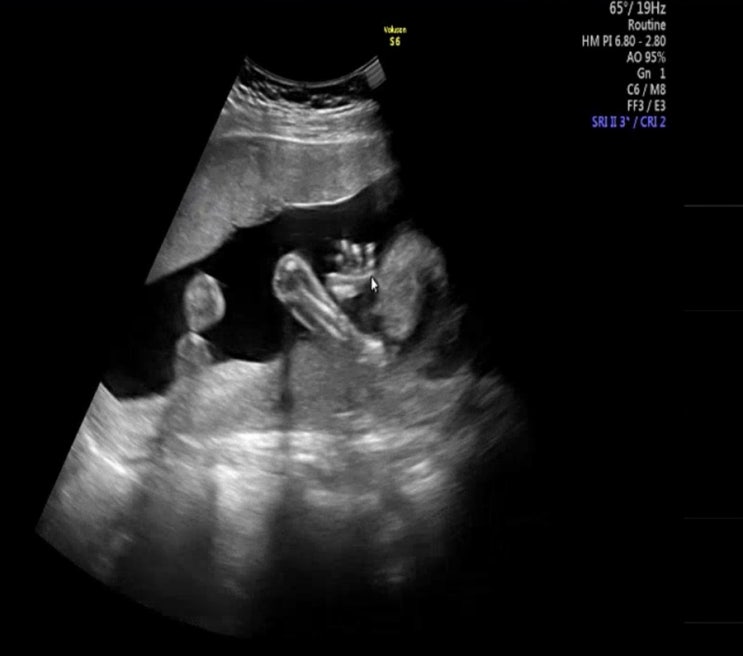

3월 13일 수요일, 37주 2일차 검진 이제 일주일에 한번씩 검진가야한다..! 가자마자 또 태동검사를 했는데 ...